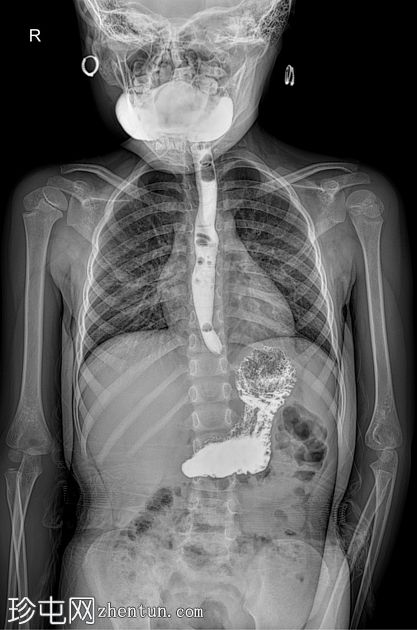

荧光透视

AP

食管体扩张,远端食管平滑收窄,呈现经典的鸟嘴状或鼠尾状外观

扩张食管内可见气液平面

造影剂进入胃排空延迟

荧光透视钡餐检查显示食管扩张,胃食管连接处平滑收窄,造影剂进入胃延迟。虽然这些特征提示贲门失弛缓症,但并非其特征性表现,尤其是在儿童中,因为下食管括约肌狭窄有时可视为正常变异。

贲门失弛缓症在儿科人群中并不常见,但对于年龄较大且存在非特异性上消化道症状的儿童,例如吞咽固体和液体食物困难、反流、体重下降或反复食物潴留,则应考虑该病。可能支持诊断的影像学征象包括:

食管均匀扩张

原发性蠕动消失

排空延迟

食管远端平滑收窄

荧光透视被认为是评估疑似贲门失弛缓症的一线影像学检查方法。